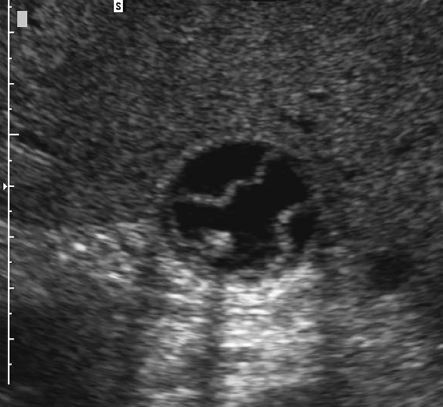

Tubular Ectasia of the Rete Testes

• The rete testes are a complex collection of small tubules that are located in the mediastinum of the testis. Fluid from the seminiferous tubules drains into the rete testis and then exits the rete testis via the efferent ductules. The efferent ductules then converge into the head of the

epididymis.

• Tubular ectasia of the rete testes is believed to be caused by some degree of outflow obstruction of the seminiferous fluid. Perhaps this is the reason why it is frequently associated with testicular cysts and spermatoceles of the epididymal head. It is also more commonly seen in patients with a history of inguinal surgery, such as hernia repairs and vasectomies.

• The key to making the diagnosis and distinguishing tubular ectasia of the rete testes from cystic testicular tumors is to note the bilateral involvement when present and to recognize the elongated shape on long-axis views of the testis.